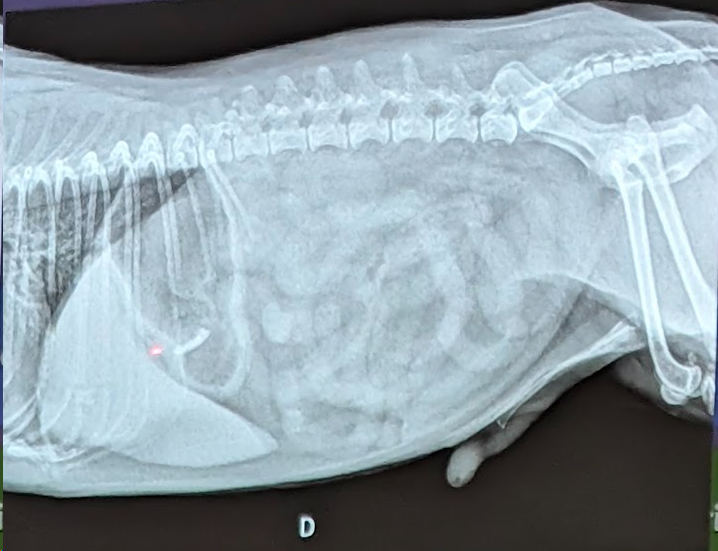

- Hay efusion pleural

- Hay Hipertensión pulmonar (dilatación y tortuosidad de las arterias pulmonares, una prominencia del tronco pulmonar y un aumento del tamaño de las cavidades derechas del corazón. En este caso se ve porque si lo comparamos con la 9a costilla vemos que es mucho mas gruesa la arteria de la derecha que la costilla)